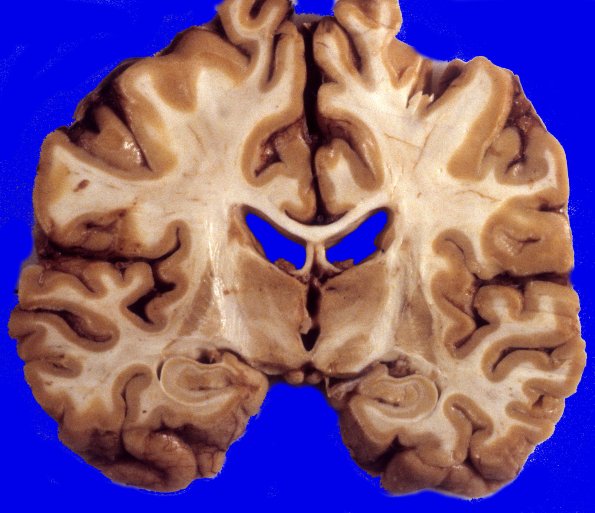

Neuronal Ceroid Lipofuscinosis (NCL)

3A4 Neuronal Ceroid Lipofuscinosis (Case 3) A1